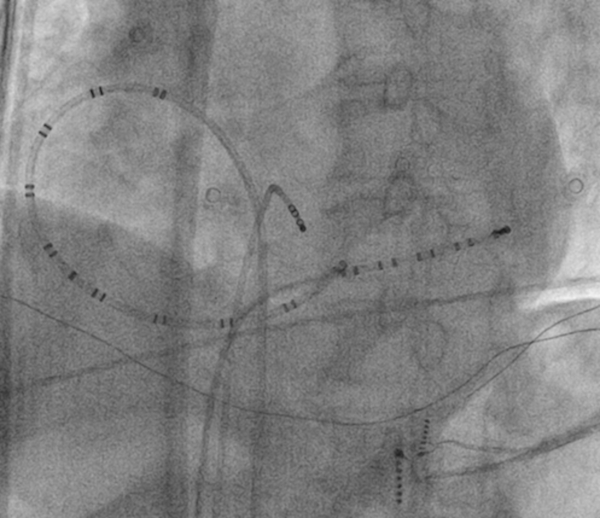

Catheters

fluoro.jpg